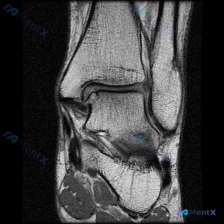

这是一张膝关节轴位T1加权MRI图像,临床提出的问题是评估是否存在软骨异常。

- 整体解剖结构:髌骨、股骨远端滑车轮廓清晰,皮质骨光滑,无骨质破坏或骨皮质中断,骨髓信号大致均匀

- 髌股关节对位正常,关节间隙无狭窄,关节软骨面显示尚可

- 周围软组织:股四头肌肌腱、内外侧支持带形态正常,Hoffa脂肪垫信号均匀,腘窝无异常肿块

- 未见明确骨髓水肿、坏死,未见半月板撕裂、韧带损伤、大量关节积液,也没有异常肿块或钙化

核心客观结论:这张单幅T1图像上未见明确的软骨形态异常(变薄、缺损、剥脱、信号中断),也没有其他明确阳性病变。